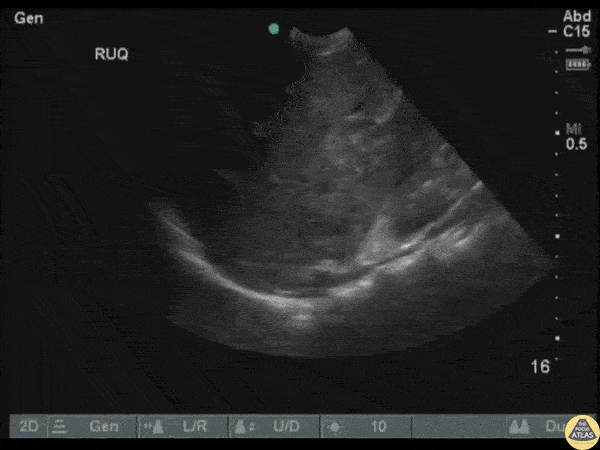

Trauma - Adrenal Hematoma

An adult male presented to the ED following a MVC with a fractured femur, right sided flank pain, and transient hypotension. FAST exam revealed an isoechoic, oval structure just cephalad to the right kidney indicative of an adrenal hemorrhage/hematoma. Image courtesy of Robert Jones DO, FACEP @RJonesSonoEM Director, Emergency Ultrasound; MetroHealth Medical Center; Professor, Case Western Reserve Medical School, Cleveland, OH View his original post here